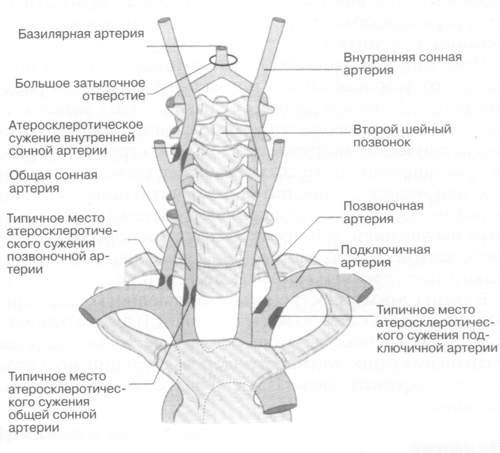

Виллизиев круг является ключевым элементом для нормального кровоснабжения всех систем нашего организма. Он образуется крупными позвоночными артериями, которые делятся на левую и правую ветви. В нормальных условиях развитие этих артерий происходит равномерно. Подключичная артерия, направляясь к черепной полости, разветвляется на входе.

Специального лечения данное заболевание не требует, так как организм обычно находит способы для компенсации кровоснабжения. Однако в редких случаях может произойти сбой, что потребует вмешательства медицинских специалистов. Сопутствующие заболевания представляют собой основную проблему данной патологии. Например, атеросклероз может усугубить ситуацию с кровообращением из-за значительного сужения сосудов. Пациенты часто отмечают метеочувствительность и проблемы со сном.

Вот они:

- подвывихи шейных позвонков и спондилолистез (вызывают деформацию позвоночного канала);

- остеохондроз (костные разрастания начинают сжимать артерию);

- окостенение, затрагивающее мембрану между позвоночником и затылком;

- образование тромбов в аномальной артерии;

- атеросклероз сосудов.